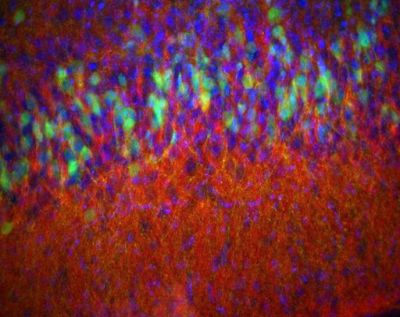

Piriform cortex, mouse -  histology slide

Piriform cortex from a 14 day old D2-eGFP (green) mouse stained for enkephalin (red) and DAPI (blue) to show nuclei. Epifluorescence.